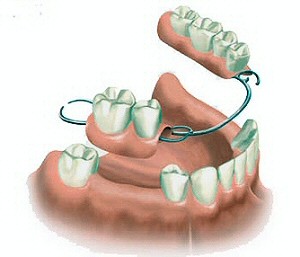

Protesi dentarie mobili parziali (Scheletrati)

Le protesi scheletrate sono realizzate per sostituire più elementi dentari persi e possono ancorarsi ai denti naturali presenti con ganci oppure con attacchi di precisione. In questo caso è richiesta la ricopertura dei denti presenti.

Le protesi scheletrate sono realizzate per sostituire più elementi dentari persi e possono ancorarsi ai denti naturali presenti con ganci oppure con attacchi di precisione. In questo caso è richiesta la ricopertura dei denti presenti.

Le protesi dentarie mobili scheletrate sono costituite da una parte metallica e da una parte di resina. La parte metallica è una lega cromo-cobalto-nikel, oppure in titanio nei pazienti allergici. Le protesi scheletrate sono realizzate con denti preformati in resina o in ceramica.